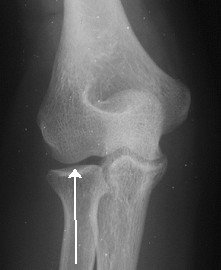

Look closely at individual parts, if dislocation look closely for tip of coronoid fragment

Look for dislocation/ subluxation of radial head

On all views (including obliques) the radial head should point to the capitellum.